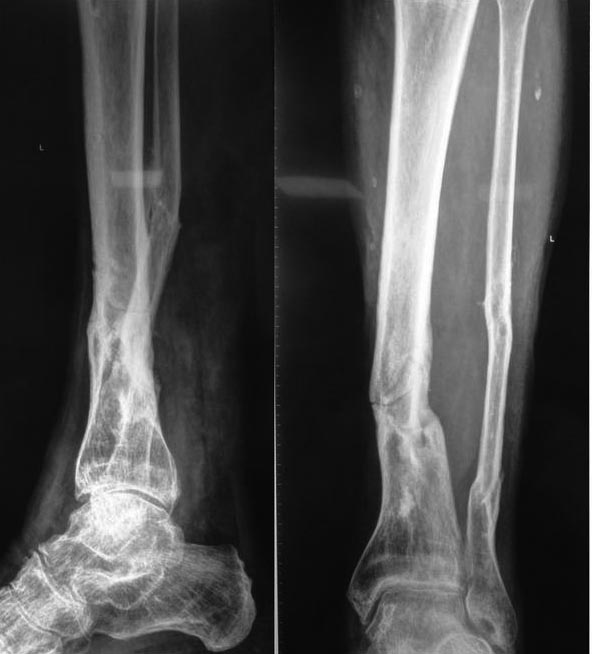

Обратился мужчина 55 лет. В марте этого года получил травму: на ногу

упало бревно. Проводили гипсовую иммобилизацию. На рентгенограммах,

выполненных в сентябре, прослеживается линия перелома. На данный момент

ходит в жестком ортезе и с тростью, болей нет. При ходьбе без ортеза,

при пальпации области перелома болей также нет.

В анамнезе: 30 лет назад открытый перелом обеих костей этой голени с

развитием инфекционного осложнения - получал хирургическое лечение. С

тех пор конечность не беспокоила. Курит. Как трактовать такую картину:

просто несращение, ложный сустав (? - нет признаков склерозирования канала)?

Какую тактику ведения выбрать: отпустить с полной нагрузкой, - есть

опасения, что рано или поздно произойдет перелом, и вопрос решится в

пользу БИОСа сам собой. Выполнить БИОС сейчас, превентивно? Спасибо.